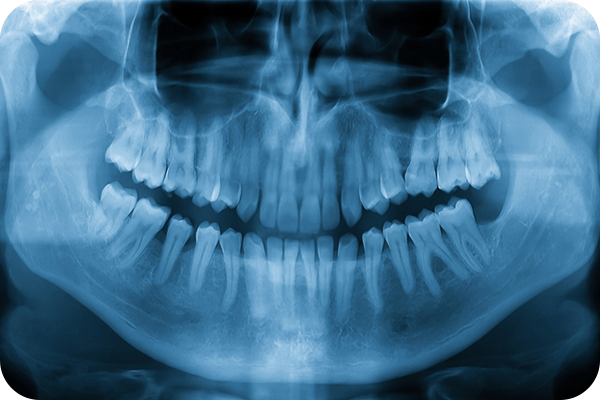

歯科用CT

根管治療では、複雑な形の根管の状態を正確に把握することが大切です。歯科用CTを使うことで、根管の状態を鮮明な3D画像で確認できます。

親知らずの抜歯

親知らずの本数や生え方は人によってさまざまで、早めに抜いたほうが良い場合もあれば、特に問題がなく経過観察で大丈夫な場合もあります。いずれにしても、親知らずの状態を正しく確認し、必要に応じて適切な処置を受けることが大切です。気になるかたは、早めに歯科医師の診断を受けましょう。